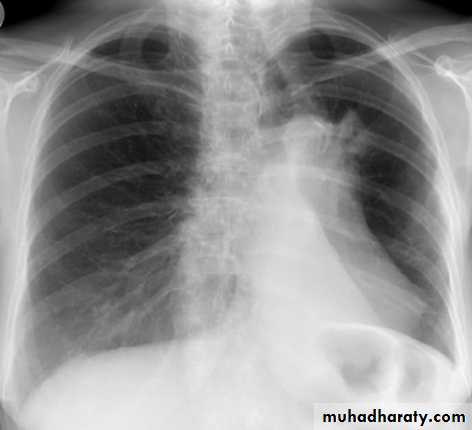

Left upper lobe collapse has distinctive features but can be challenging to identify on chest radiographs by the uninitiated.

Radiographic features

The left upper lobe collapses anteriorly becoming a thin sheet of tissue apposed to the anterior chest wall, and appears as a hazy or veiling opacity extending out from the hilum and fading out inferiorly . It thus reverses the normal slight increase in radiographic density seen as you move down the lung (due to increased thickness of the chest soft tissues).

Parts of the normal cardiomediastinal contour may also be obliterated where the left upper lobe, particularly the lingula abut the left heart border. The anterior parts of the aortic arch are also often obliterated from view.

In some cases the hyperexpanded superior segment of the left lower lobe insinuates itself between the left upper lobe and the superior mediastinum, sharply silhouetting the aortic arch and resulting in a lucency medially. This is known as the HYPERLINK "http://radiopaedia.org/articles/luftsichel-sign" luftsichel sign.

The left hilum is also drawn upwards, resulting in an almost horizontal course of the left main bronchus and vertical course of the left lower lobe bronchus.

Non-specific signs indicating left sided atelectasis will also be present, including:

elevation of the hemidiaphragm

'peaked' or 'tented' hemidiaphragm: HYPERLINK "http://radiopaedia.org/articles/juxtaphrenic-peak-sign" juxtaphrenic peak sign

crowding of the left sided ribs

shift of the mediastinum to the left

On lateral projections the left lower lobe is hyperexpanded and the oblique fissure displaced anteriorly. There is associated increase in the retrosternal opacity.